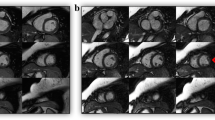

All evaluated images received a quality score ≥ 3. Examples with overall excellent image quality scores are shown in Fig. 3a and b. Average image quality scores for 4D flow-cine and bSSFP-cine images are given in Table 2 and demonstrate differences in systolic short-axis as well as systolic 4-chamber view images. Representative examples of systolic 4D flow-cine short-axis and systolic 4-chamber bSSFP-cine images with lower image quality scores are shown in Figures 3c and 3d, respectively.

Representative examples of images with adequate to excellent image quality scores. End-diastolic and end-systolic LV 2-chamber, 4-chamber and short-axis images in 4D flow-cine (a) and bSSFP-cine (b) series with excellent quality scores. 4D flow-cine short-axis images of adequate quality (c). bSSFP-cine images (3T off-resonance band in the left atrium is marked by arrow) of good quality (d).